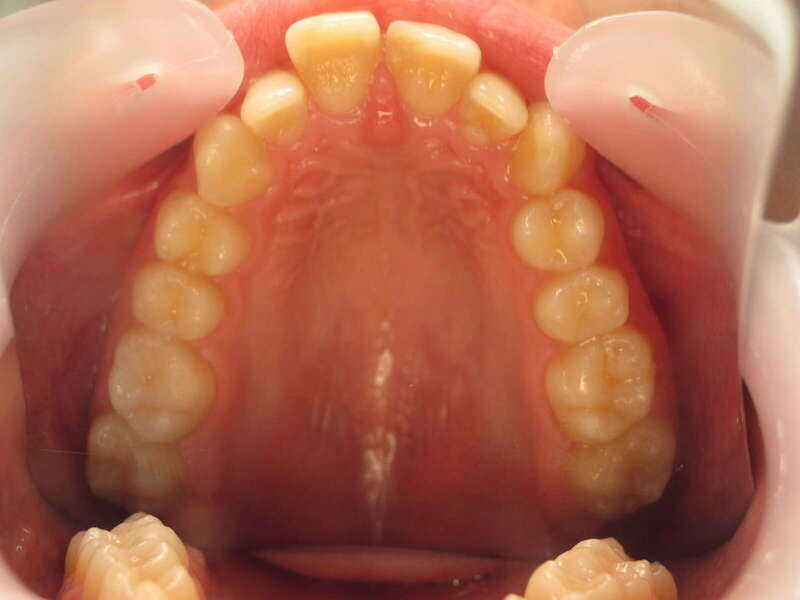

Cas n°1 traité par aligneurs (interception) - enfant

Ce cas d’interception chez un enfant de 8 ans démontre l'efficacité des aligneurs pour corriger des troubles fonctionnels précoces. Le diagnostic présentait des inversions d'articulé provoquant une déviation de la mandibule vers la gauche et un décalage des milieux.

Grâce à une coopération exemplaire et un traitement totalement indolore, l'expansion de l'arcade a permis de recentrer la mâchoire. Cette intervention a littéralement remis la croissance sur les rails, neutralisant le risque d'asymétrie faciale squelettique.